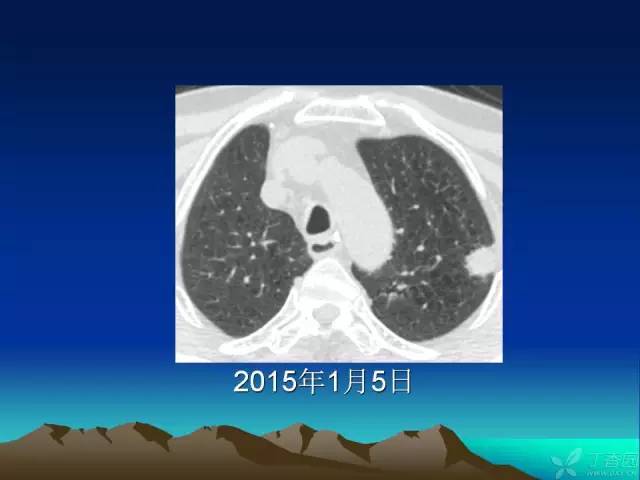

【PPT】早期肺癌易漏诊征象分析